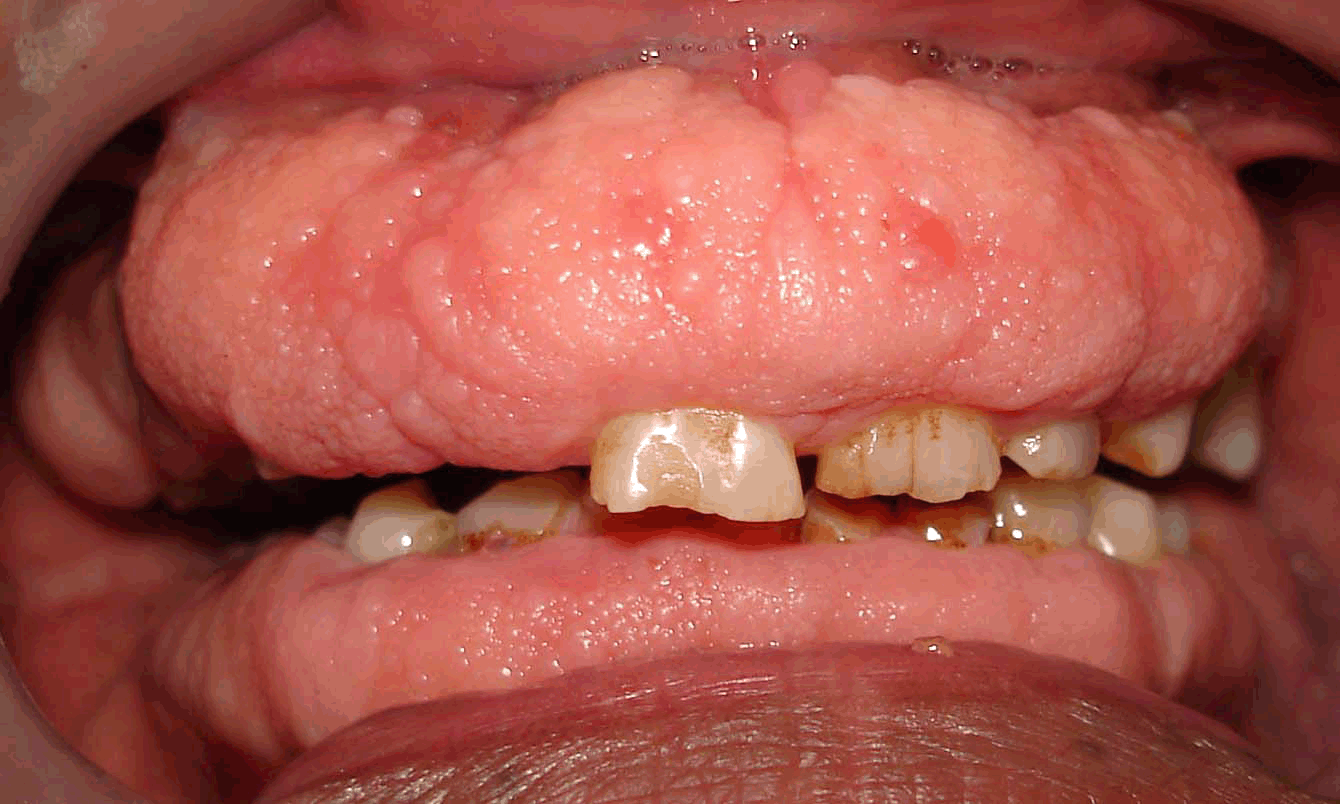

SCP-7202中期病例。

描述: SCP-7202是一种异常性的牙科病症,特征为牙龈发生快速的过度生长。SCP-7202产生的过剩牙龈组织一般多孔、敏感且易于出血。由于发展速度极快,若无手术干预,牙龈组织可能会在数周之内将牙齿闭塞、妨害下颌活动。